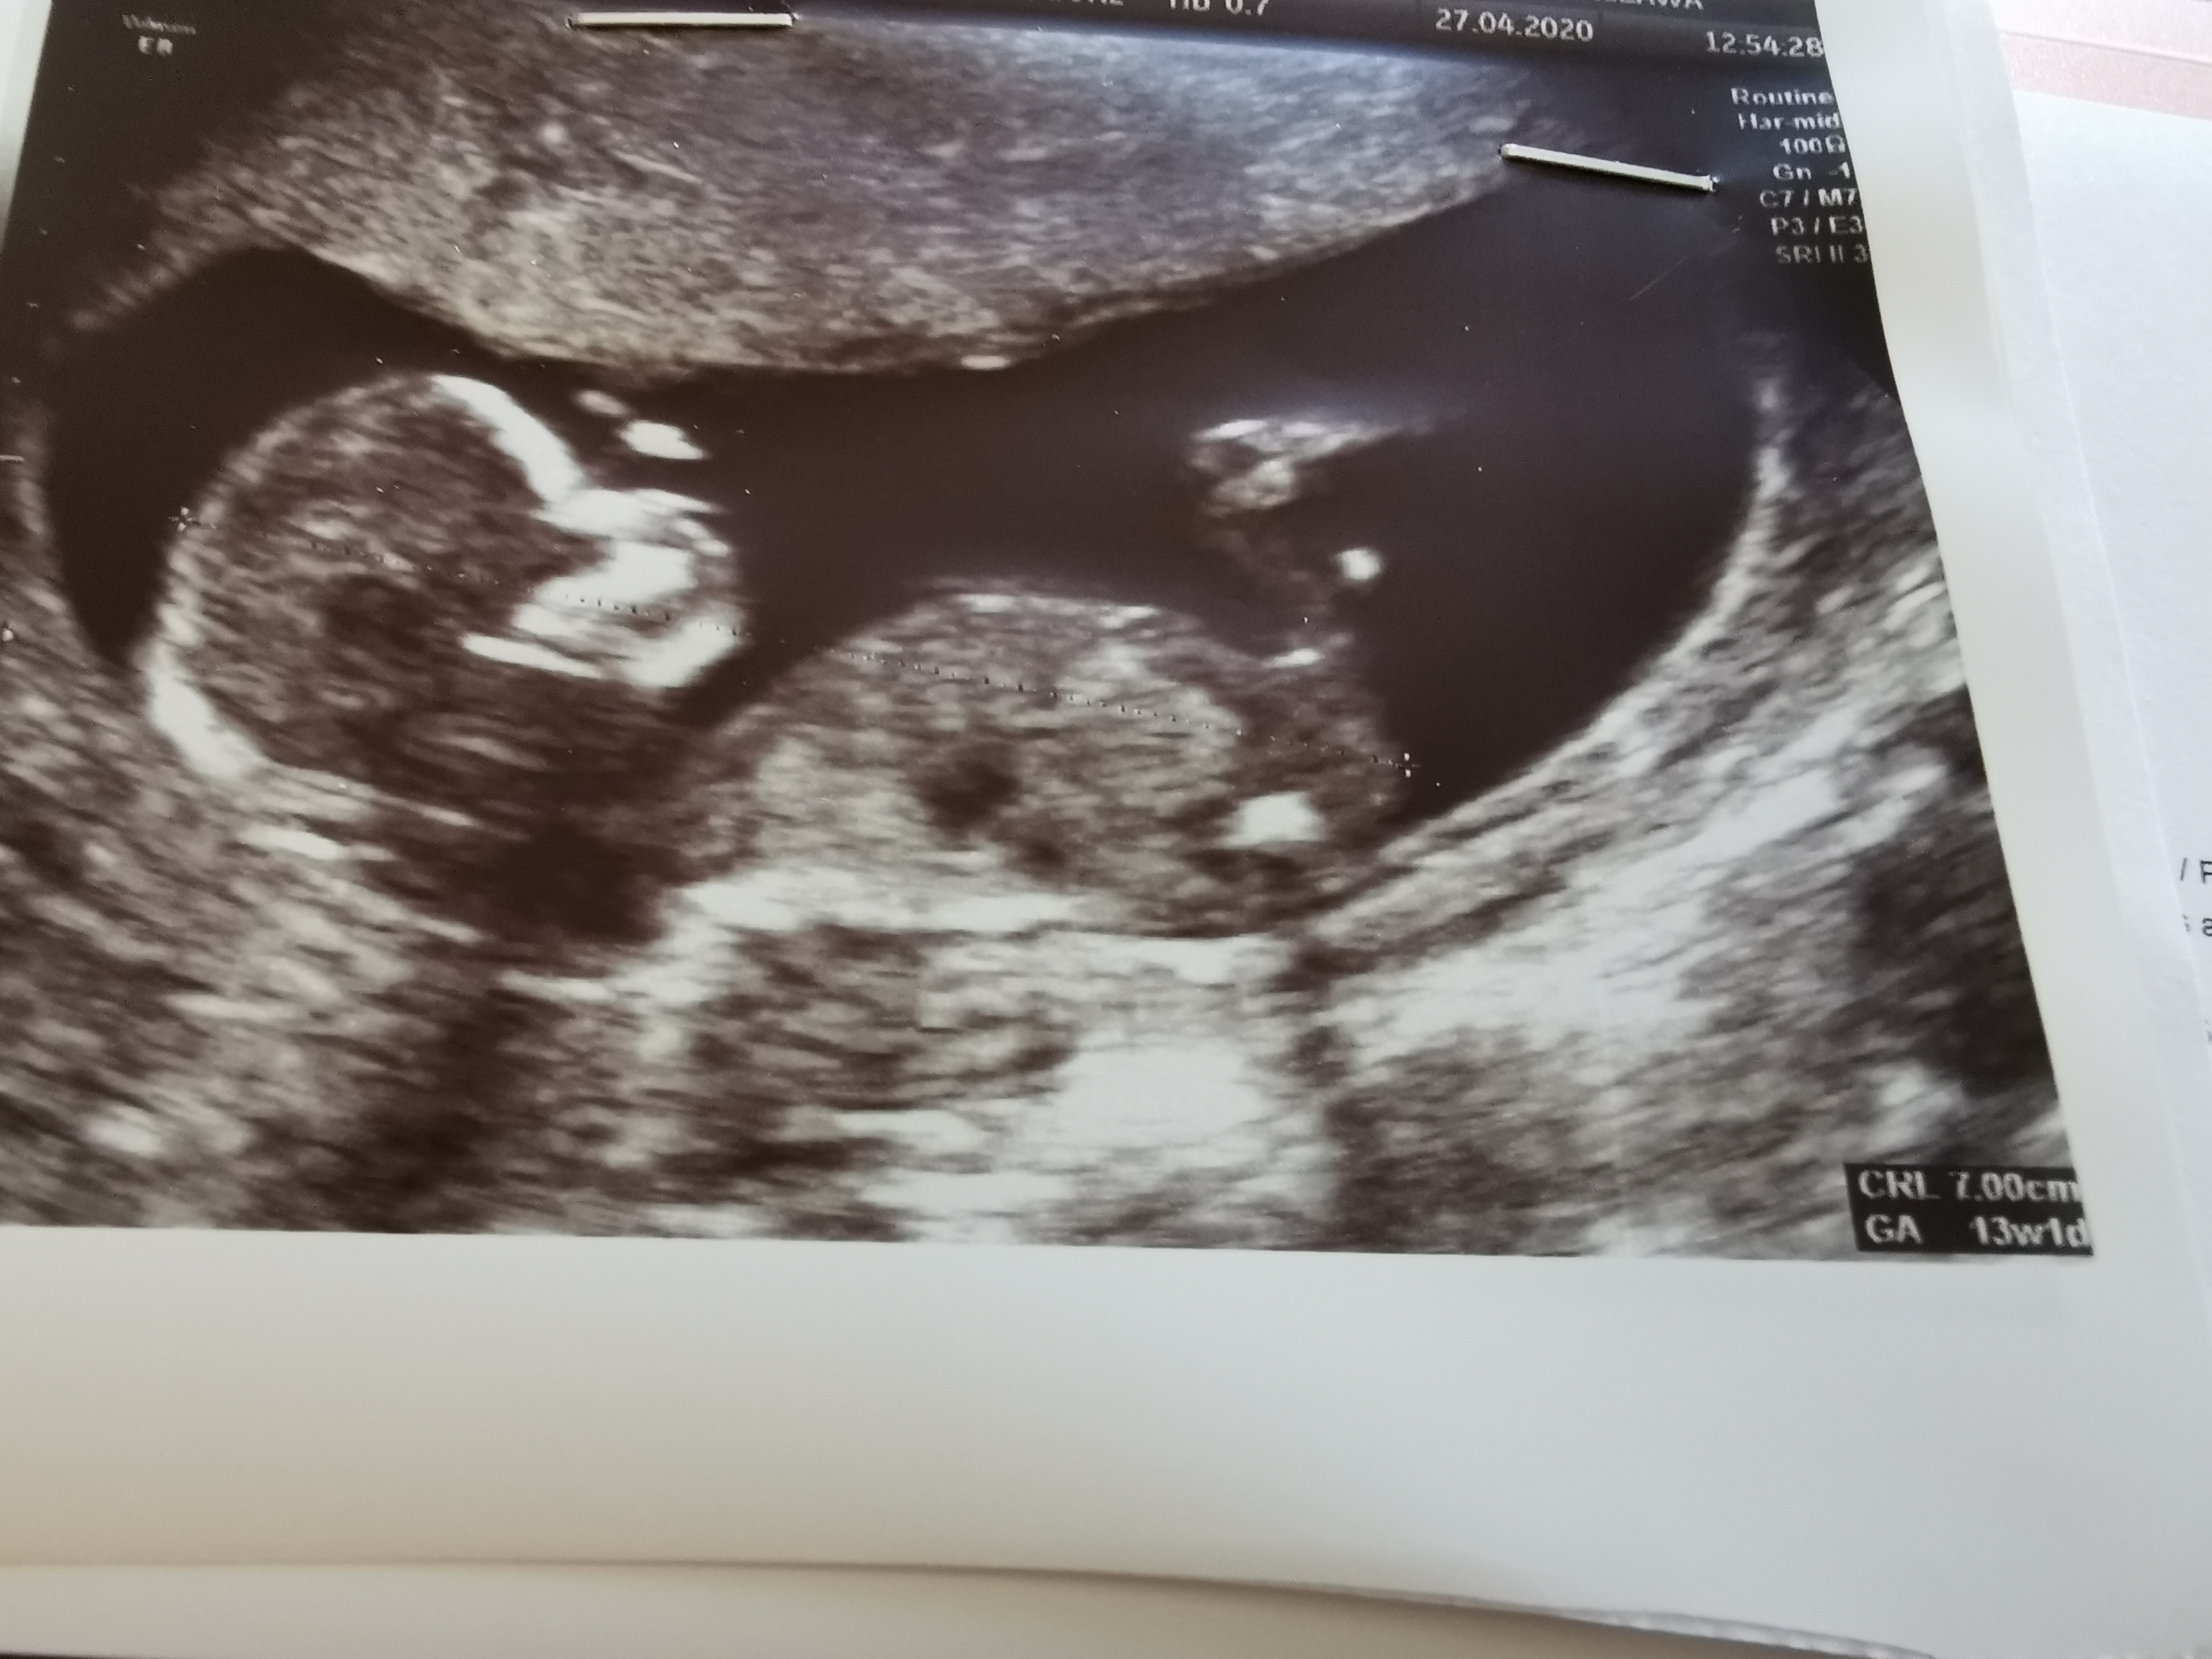

ja już po usg. Wszystko prawidłowo, młody długi bo ma już 7cm. Bylam trochę za wcześnie, więc przed wpadłam na chwilę do Pałaszewskiego, bo on nawet nie wiedział ze się udało, bo byl wtedy na L4. Jak mnie zobaczył i zmierzył wzrokiem to wielkie oczy i że szok

Oto Mały Dziabąg

, wciąż jeszcze bez imienia, bo nadal nie wiemy